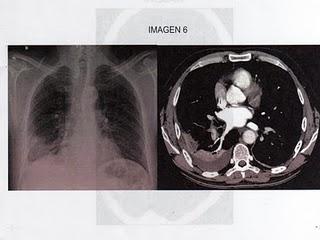

11.- Hombre de 63 años, fumador importante, intervenido hace un mes de neoplasia de sigma, acude al servicio de Urgencias por presentar disnea de 48 horas de evolución que comenzó bruscamente y se ha acompañado de esputo hemoptoico y dolor torácico derecho de características pleuríticas. En la exploración, el paciente está ansioso, sudoroso, cianótico y se constata temperatura de 37.8ºC, una frecuencia respiratoria de 34 rpm y una frecuencia cardiaca de 120 lpm. La presión arterial es de 100/55. En la ACP, se comprueba la existencia de taquicardia, un 2º ruido pulmonar más fuerte y un roce pleural dcho. La GAB a aire ambiente: PH 7.32, PCO2 de 28, PO2 de 50. En el ECG, se observa una onda T invertida de V1 a V4. Tras Oxígeno, la saturación de O2 es de 90%. Se realiza Rx de tórax y TC espiral de tórax con contraste. De las siguientes opciones, en relación al manejo de este paciente, ¿cuál es la más acertada?1.- VMNI y broncodilatadores2.- Cefotaxima iv 2 grs/8 horas y Azitromicina iv 500 mgrs/día y tubo de drenaje pleural.3.- Morfina iv 5 mgrs en dos minutos y luego, PC de dopamina a 2-5 mcgrs/kgr/min4. Activador tisular del plasminógeno 100 mgrs iv en dos horas, seguido de anticoagulación.5.- Aspirina 325 mgrs por vía oral y NTG sublingual. Respuesta correcta: 4¿Por qué? Se trata de un cuadro de tromboembolismo pulmonar de libro. El paciente tiene dos factores de riesgo mayor, que son la cirugía y el tumor, aparte de ser fumador. Llega a Urgencias, hipotenso, taquicárdico, taquipneico, con una disnea brusca. La febrícula es resultado del estado de inflamación secundario, NO de una neumonía (por lo que, la opción 2 es incorrecta). Las pruebas lo confirman, así como el hecho de que no mejora con oxígeno. En la imagen de TC con contraste, se ve que el contraste tiene un defecto de llenado. Por lo tanto, la opción más adecuada es aquella que trata el trombo, es decir, la 4.